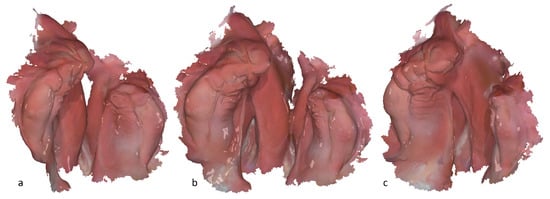

Figure 3. Socketed model of a left-sided cleft lip, jaw, and palate: (a) tailed view with the focus on the smaller segment; (b) occlusal view of the small and large segment; (c) tailed view with the focus on the large segment.

The model preparation ensures that the data are properly prepared and aligned for accurate measurement. Subsequently, the IOS data obtained are imported into the OnyxCeph3™ software for processing and preparation for the digital measurement (Figure 1, Step 2). The edges of the IOS are trimmed to eliminate any excess or irrelevant data. Subsequently, a 3D model is generated from the 3D data set using a base (Figure 3, Step 3, and Figure 1).